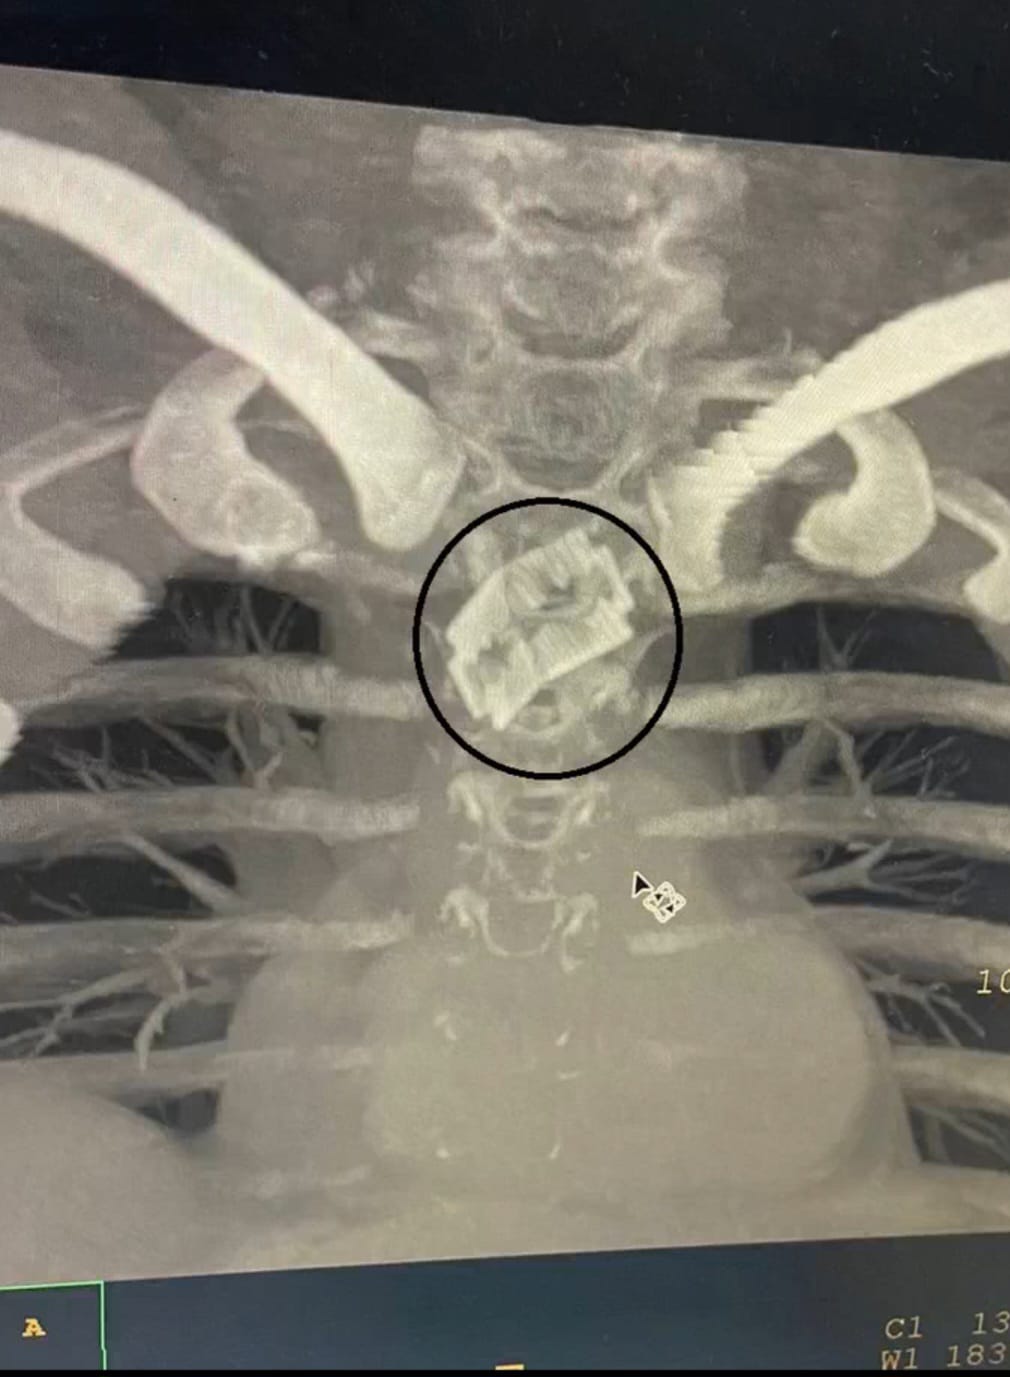

डाक्टरों ने मरीज का ऑपरेशन कर ब्लेड को आहार नाल यानी (खाने की नाला) से सफलतापूर्वक बाहर निकाला।ऑपरेशन के बाद मरीज बिल्कुल ठीक है। यह जानकारी इंद्रेश अस्पताल के नाक कान गला रोग विभाग के डाॅ शरद हरनोट ने दी। 26 वर्षीय पुरुष भूलवश खाने के साथ रेज़र ब्लेड निगल गए। खाने की नली में फंसे धारदार ब्लेड की वजह से मरीज के जीवन पर बन आई थी।

इंद्रेश अस्पताल के नाक कान गला रोग विभाग के डाक्टरों ने प्रारम्भिक जांच में पाया कि ब्लेड सांस की नली के पास महत्वपूर्ण खून की सबसे बड़ी नस के काफी पास अटकी हुई है। इंद्रेश अस्पताल के नाक कान गला रोग विभाग के डॉक्टरों ने 26 वर्षीय पुरुष की खाना खाने की नली में फसे रेजर ब्लेड को निकालकर मरीज को नया जीवन दिया है ।

श्री महंत इंद्रेश अस्पताल के असिस्टेंट प्रोफेसर व ईएनटी सर्जन डॉक्टर शरद हरनोट ने सीनियर रेजिडेंट डॉ. फातमा अंजुम के साथ मरीज की सफल सर्जरी की और एंडोस्कोपी द्वारा पूर्ण रेजर ब्लेड को खाने की नली से बाहर निकाला। मरीज के माता पिता ने डॉक्टरों व श्री महंत इंद्रेश अस्पताल का आभार जताया।

ऑपरेशन अत्यधिक जटिल था। ऑपरेशन के बाद मरीज को नाक की नलकी द्वारा उपचार एवम खाना शुरू किया गया। ऑपरेशन के बाद मरीज बिल्कुल ठीक है।